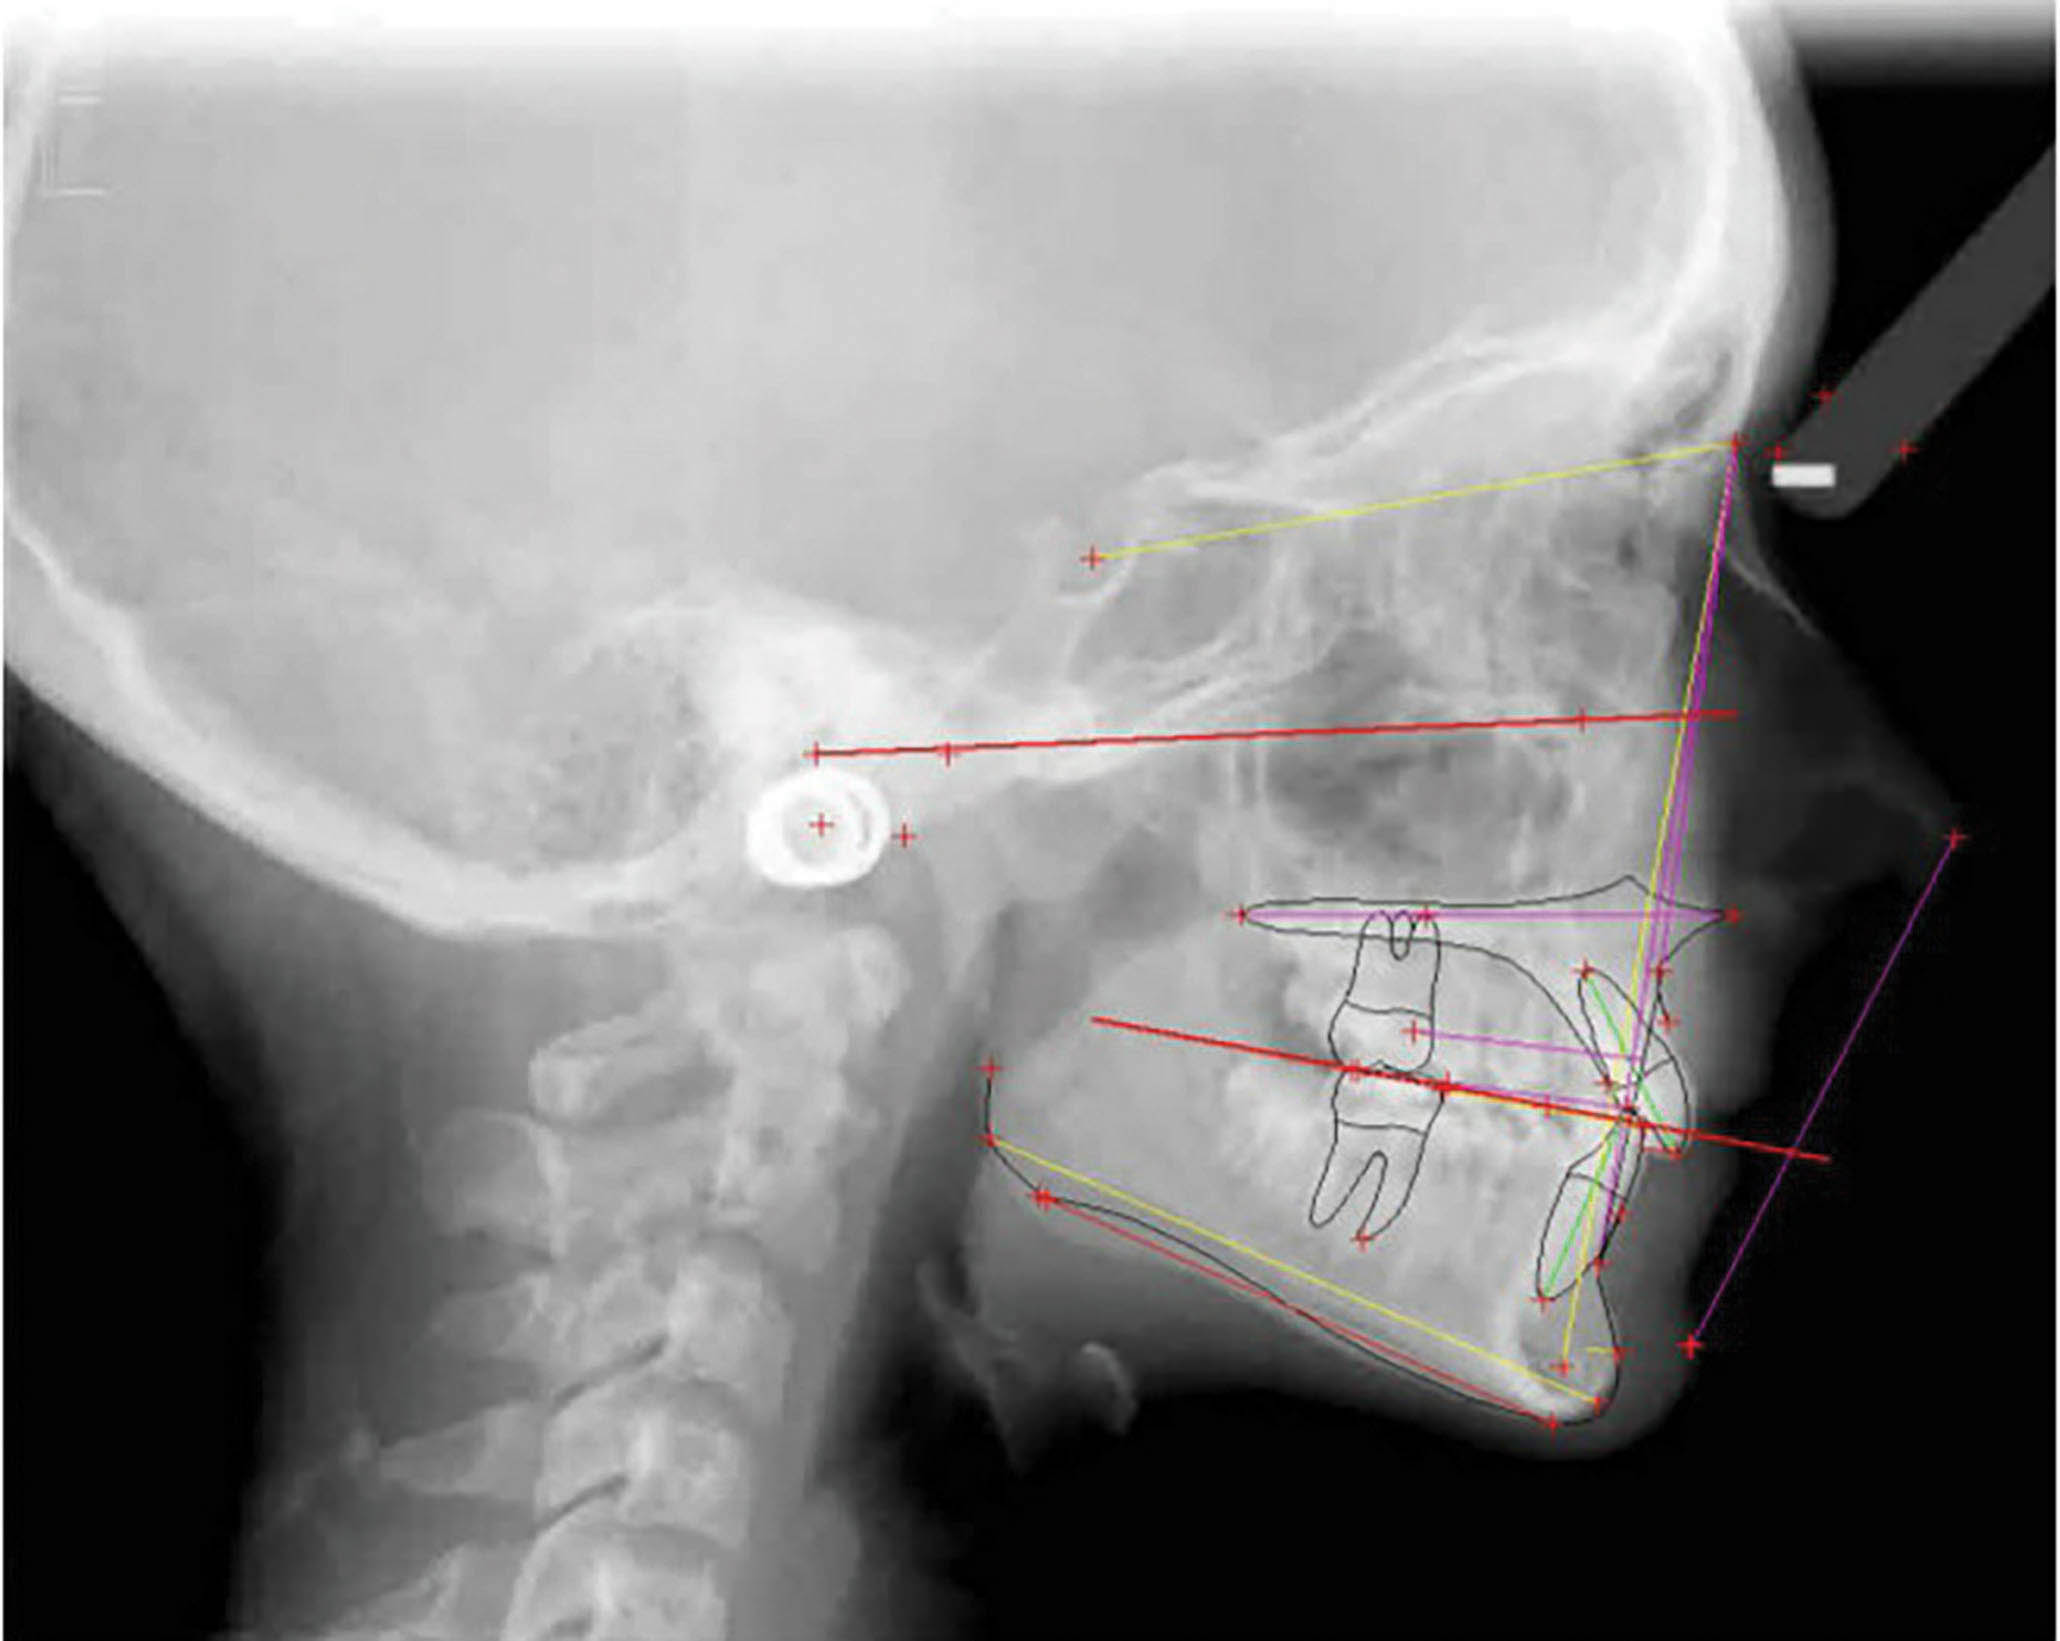

عکس OPG پایان کار (شکل 66-6) طبیعی است. سوپرایمپوز نمودن لترال سفالومتریها (شکل 67-6) پروترود شدن انسیزورهای پایین را نشان میدهد که هم برای رفع کرادینگ و هم برای اینترود نمودن نسبی قدامیها مفید بود.

درمان بیمار ۲۴ ماه به طول انجامید و یک قالب گیری مجدد نیز داش

شکل 67-6